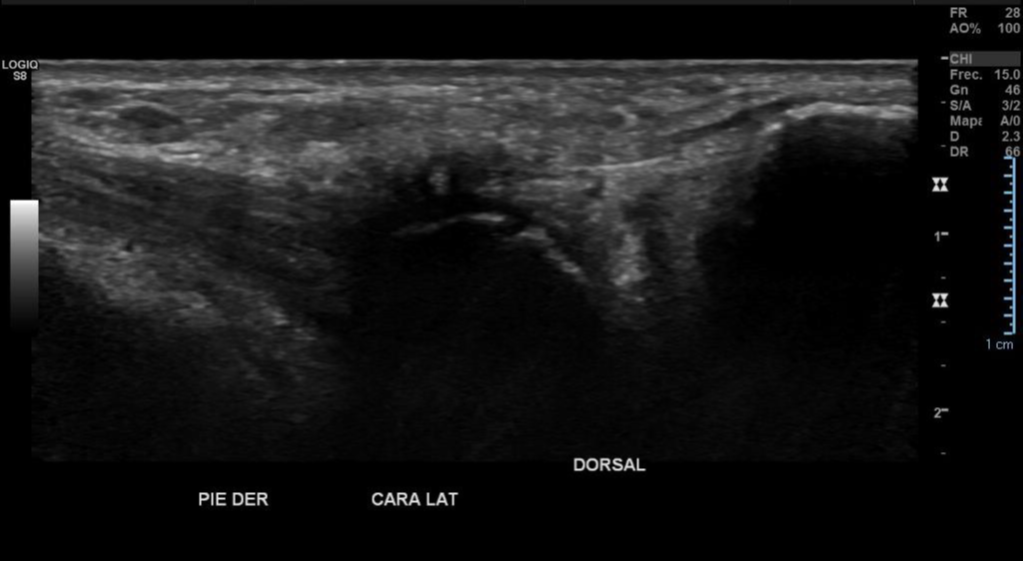

Hallazgos: Piel y tejido celular subcutáneo sin alteraciones significativas.

Planos musculares respetados.

Espacios articulares de amplitud normal y bordes regulares.

No hay signos de derrame articular.

Imagen con aspecto de os peroneo de contornos corticales irregulares, con cambios inflamatorios de las partes blandas adyacentes, pudiendo estar en relación a fractura a este nivel.

Impresión diagnóstica: Imagen con aspecto de os peroneo de contornos corticales irregulares, con cambios inflamatorios de las partes blandas adyacentes, pudiendo estar en relación a fractura a este nivel. Se sugiere evaluar con radiografía.